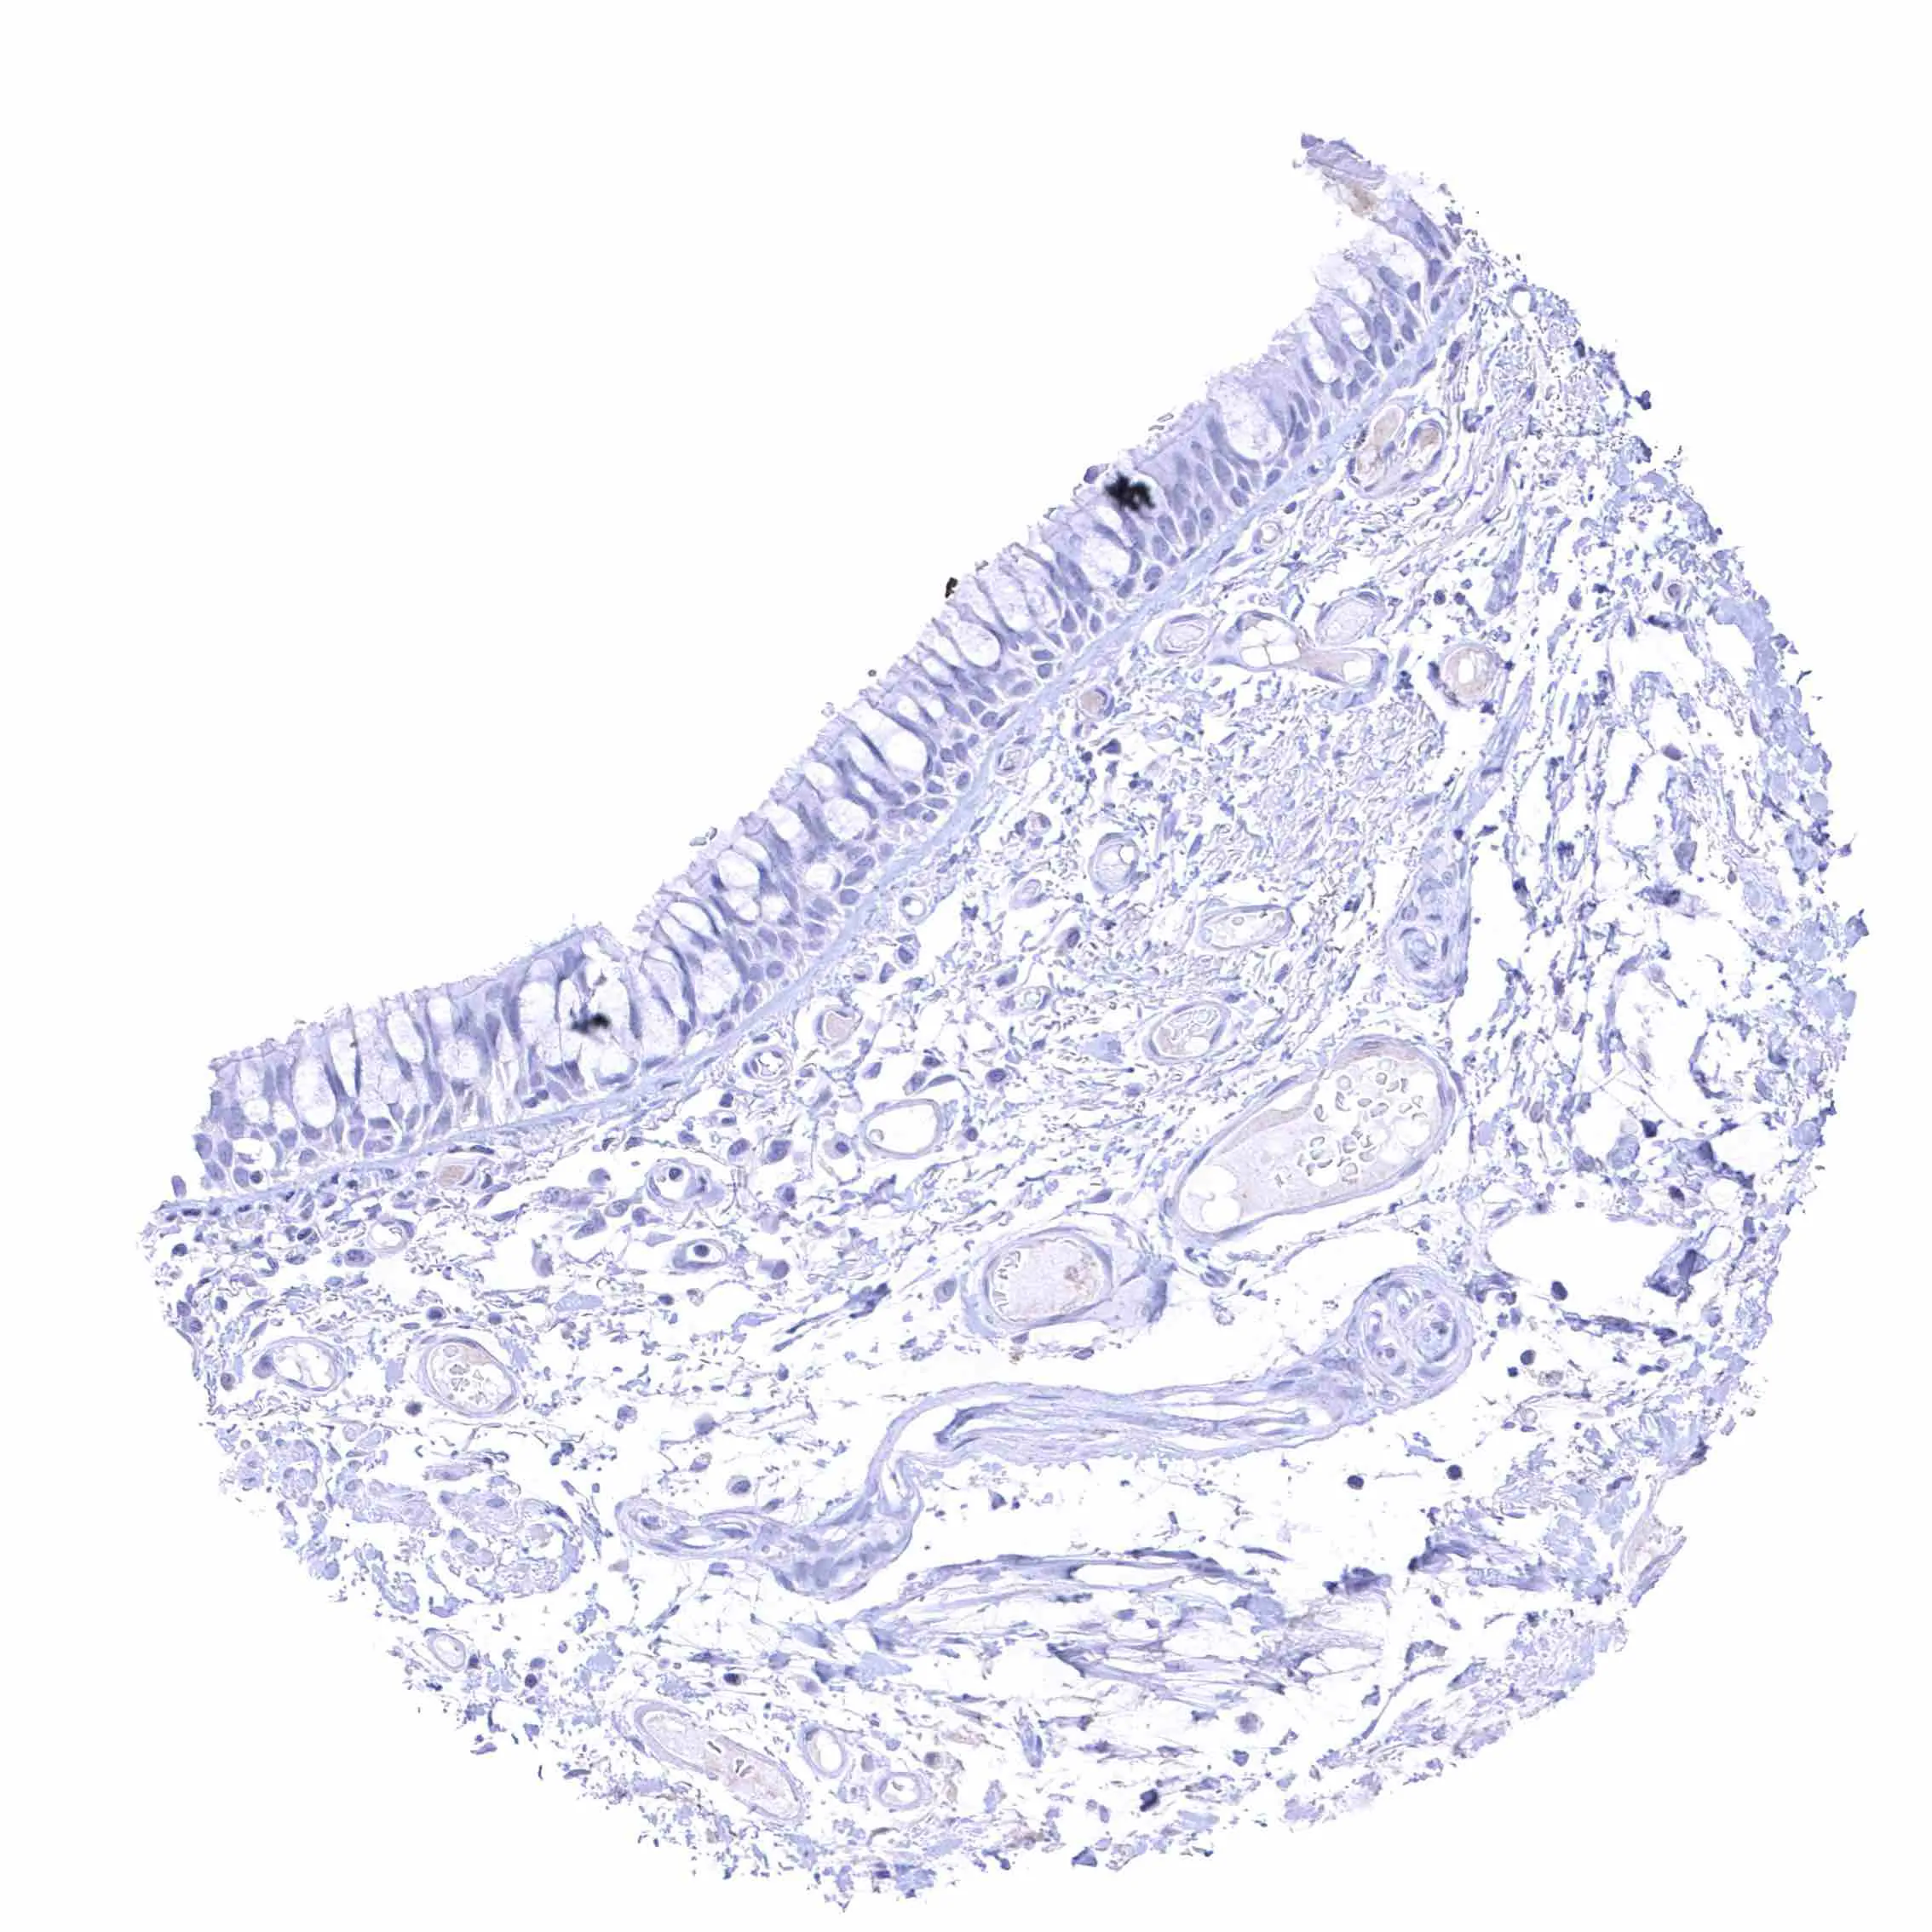

Appendix, mucosa

Appendix, muscular wall